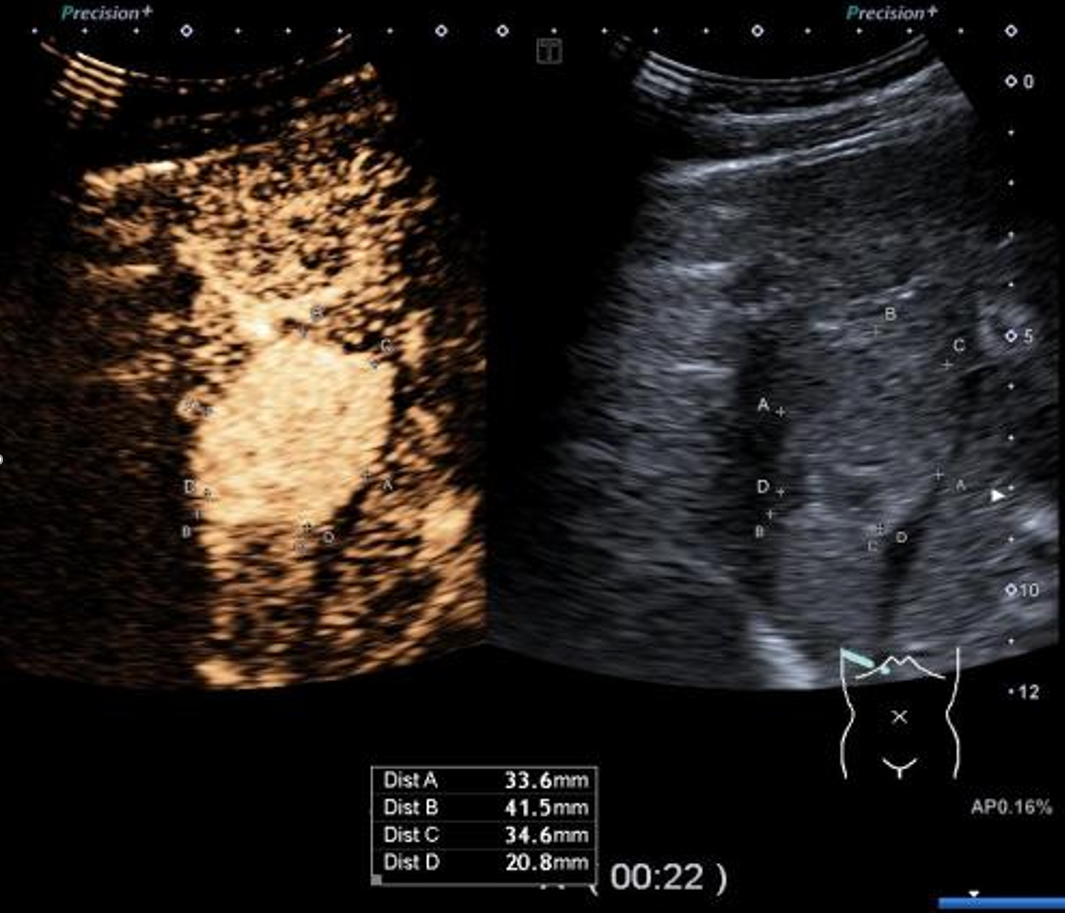

▲患者术前超声造影显示富血供